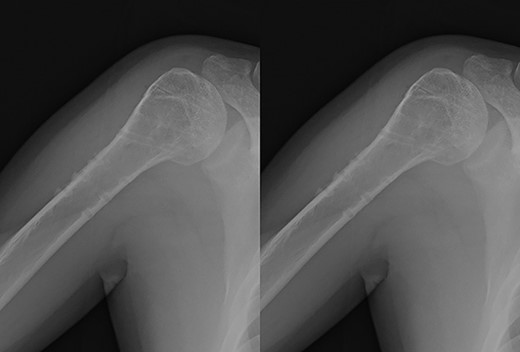

A 39-year-old man was transported via ambulance after being hit by a car. The radiographs revealed a one-part proximal humeral fracture with displacement at the surgical neck (Fig. 1). However, computed tomography (CT) revealed humeral head impression fracture and lesser tuberosity fracture in addition to a surgical neck fracture (Fig. 2). In addition, 3D-CT revealed that the collapse occupied approximately 20% of the articular surface with no glenoid defect (Fig. 3). Therefore, we first performed arthroscopic-assisted reduction and internal fixation of the humeral head impression fracture, followed by open reduction and internal fixation (ORIF) of the proximal humeral fracture.